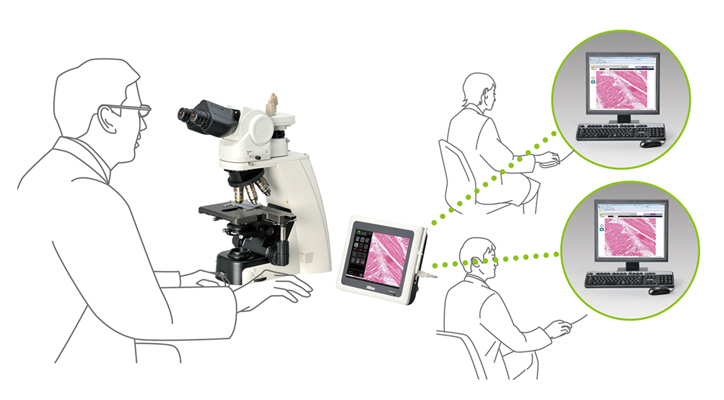

病理学通过网络数字化